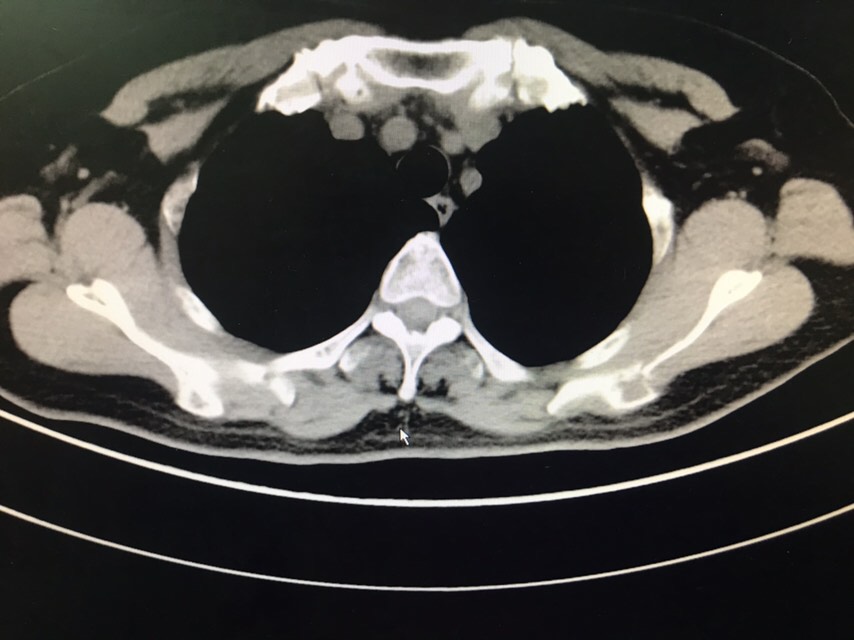

查体无特殊。辅助检查:PET-CT:1、部分颅骨、部分颅底骨质、双侧下颌骨、双侧肩胛骨、双侧锁骨、双侧肱骨上段、双侧多肋骨、胸骨、双侧髂骨、骶1棘突、双侧耻骨部分骨质虫蚀样、溶骨样破坏伴部分破坏骨质FDG代谢异常增高;上述改变考虑多发性骨髓瘤可能性大,请结合临床或右侧肋骨病灶活检。2、甲状腺右叶稍低密度结节影,无FDG代谢异常增高,多为良性病变,建议专科检查;3、双侧口咽壁对称性FDG增高,无确切占位征象,考虑为炎性改变;4、右肾错构瘤;5、脊柱部分骨质增生。骨髓涂片:目前BM示原始浆细胞比例增高8%,成熟红细胞呈缗钱状排列。骨髓活检:取材骨髓组织增生较低下,三系细胞增生均较低。骨髓流式:标本中若表达CD28,不表达CD19、CD117、cLambda、CD27、CD81、CD20、CD45,符合浆细胞肿瘤表型,正常浆细胞占有核细胞娥0.16%;流式检测中浆细胞易被破坏,比例可能低于形态学,请结合形态及免疫固定电泳结果。免疫球蛋白定量:IgG 12.6g/L,IgA 2.05g/L,IgM 0.94g/L,IgE 5.0g/L。血清固定电泳:未见IgG、IgA、IgM、KAP轻链、LAM轻链单克隆成分。尿固定电泳:在LAM区可见一条单克隆KAP轻链成分。血清游离轻链:游离KAP轻链 3800mg/L,游离LAM轻链16.00mg/L、游离KAP轻链/LAM轻链 237.5,尿游离轻链:游离LAM轻链 4100mg/L,游离LAM轻链9.13mg/L、游离KAP轻链/LAM轻链 449.069。